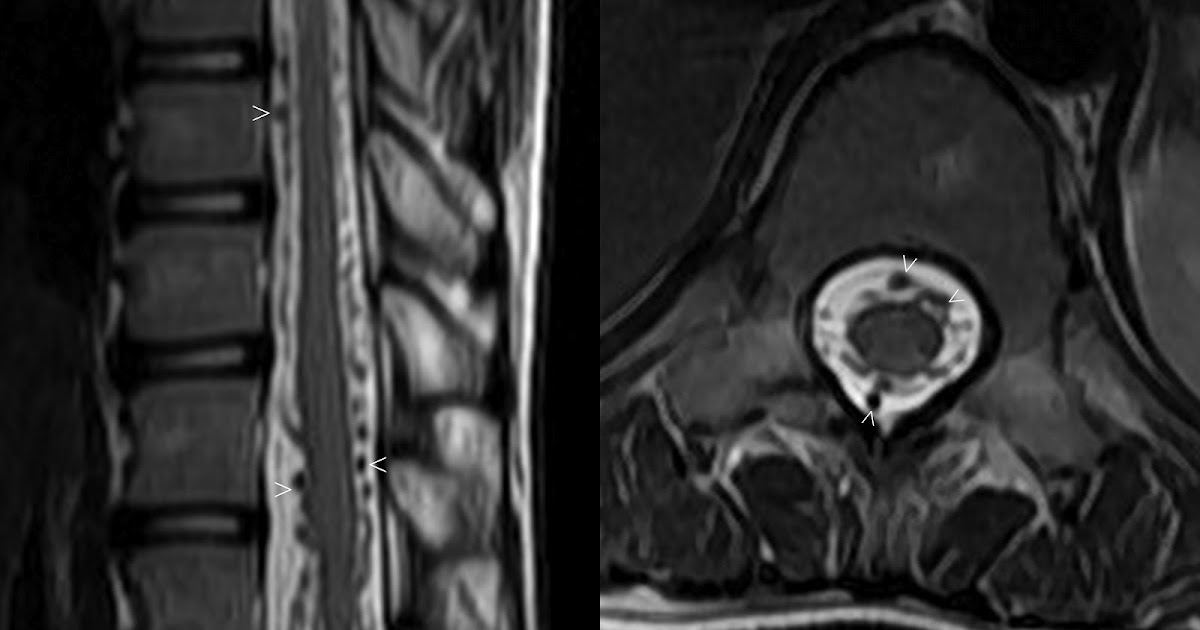

spinal dural AVF

present with gradual but progressive pain, leg weakness/numbness, bladder/bowel changes

flow voids on T2

can see intramedullary hyperintensity due to edema, often involving conus

confirmed with DSA